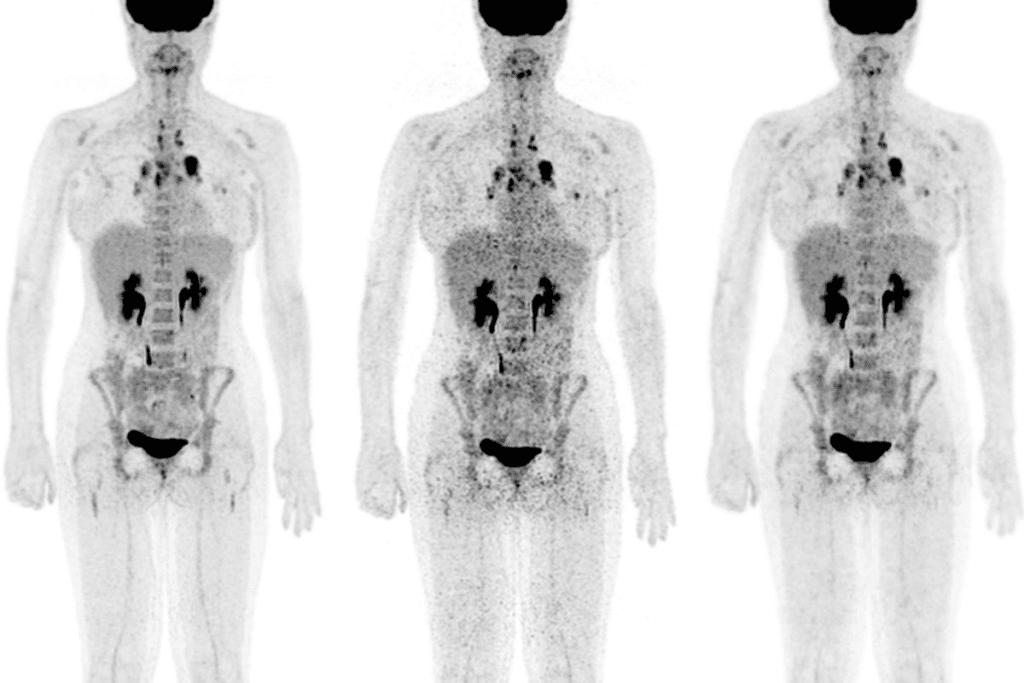

Cancer Detection and PET/CT Imaging

PET and CT scans together have changed how we find and treat cancer. We use PET/CT imaging to get a full picture of cancer. This method combines PET’s function info with CT’s body details, giving us a clearer view of the disease.

How Cancer Cells Appear on PET Scans

Cancer cells use more energy than normal cells, making them show up on PET scans. We use a special tracer, FDG, that cancer cells take up more of. This makes cancer cells show up as “hot spots” on the scan.

Staging and Evaluating Cancer Spread

Doctors need to know how far cancer has spread to make the right treatment plans. Accurate staging is key to finding the best care for cancer patients. PET/CT scans help us see how far the disease has spread, which is vital for treatment choices and patient results.

Determining the Extent of Disease

PET/CT scans are essential for finding out how far cancer has spread in the body. They combine PET scans’ functional info with CT scans’ anatomical details. This gives us a full picture of the disease, helping us figure out the cancer’s stage.

Identifying Metastasis Throughout the Body